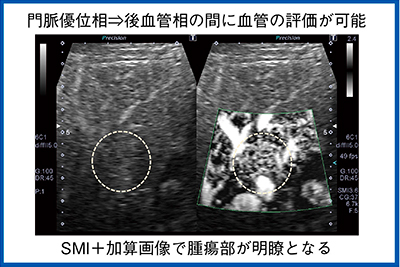

SMIは淡い微細な変化の把握に有用であるが,ROIの背景のBモードを消して血管構築を見るため,超音波検査の基本であるBモードも同時に観察できる2画面表示を推奨する。造影検査においても2画面表示とすることで,Bモードで腫瘍濃染を,SMIで不整血管を見ることができる。SMIを評価するタイミングとしては,門脈優位相と後血管相の間にSMI加算画像を取得している。従来の検査プロトコールを妨げることなく,腫瘍部の血管構築を観察することができる(図5)。

図8は門脈優位相から後血管相の間に観察したものだが,SMIはこのように明瞭な放射状の血管走行をボタン1つでいつでも加算画像で確認でき,簡単に評価することができる。